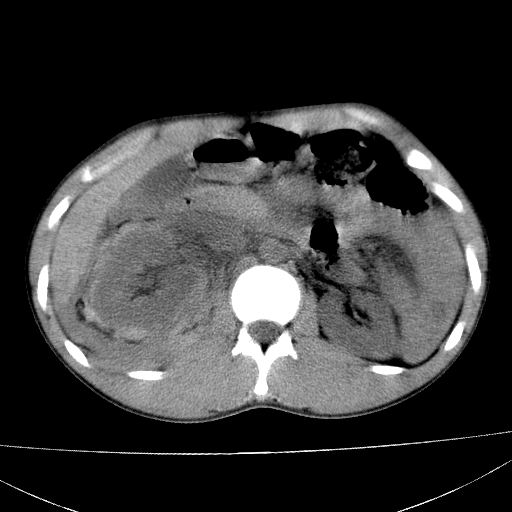

标题: CT15860:男,21岁,腹部外伤2小时伴胸疼。 [打印本页]

标题: CT15860:男,21岁,腹部外伤2小时伴胸疼。

肝脏及肾脏明显有损伤性改变并激发腹腔内积液(血),以肝脏撕裂及肾周积血显著。

1)肝破裂伴腹腔积液(血)。2)右肾破裂伴右肾包膜下及肾周血肿。3)腹部空腔脏器穿孔可能。4)右侧少量胸腔积液(血)。

肝肾挫裂伤,右肾周及包膜下血肿,腹腔积液,不排除空腔脏器穿孔,建议行增强检查

1肝挫伤伴腹腔积液。2右肾挫裂伤伴右肾包膜及肾后间隙肿血肿。3右肾脏周围的积气,十二指肠显示结构不清,考虑十二指肠降部破裂可能性大。